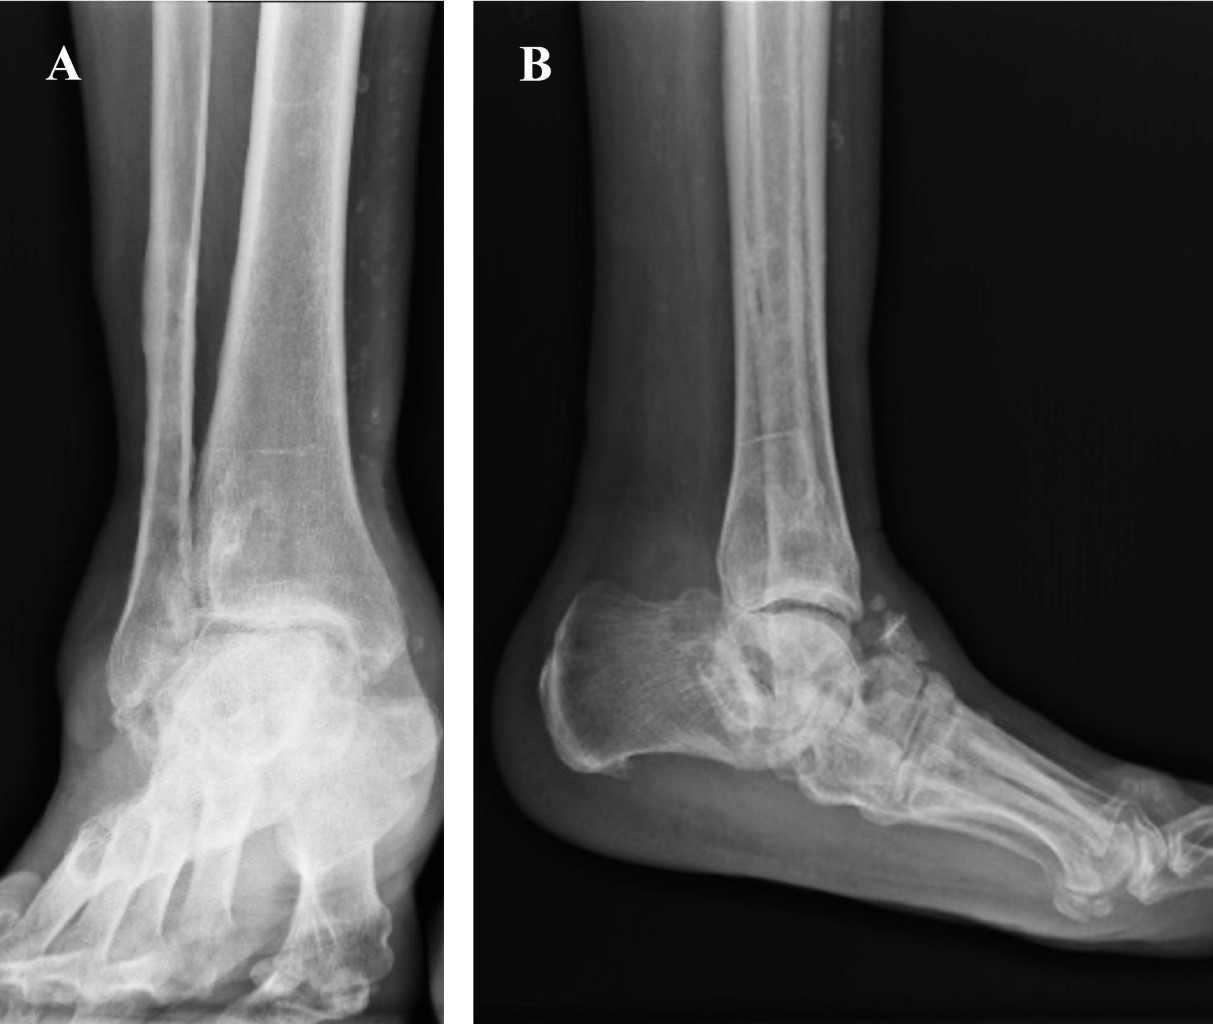

Las radiografías se consideran el método de diagnóstico más útil. Permite identificar el área de compromiso, evalúa la calidad ósea y si el proceso es agudo o crónico, el cual puede ser complementado con una tomografía axial computarizada (Figura 1).

Se analizaron 11 casos de pacientes con artropatía de Charcot tratados con clavo centromedular retrógrado (Figura 2) de los cuales ocho (72.7%) correspondieron al sexo femenino y tres (27.3%) al masculino. La edad mínima fue de 31 años y la máxima de 68 años con media de 53.2 ± 11.4 años.

Figura 1

Figura 2